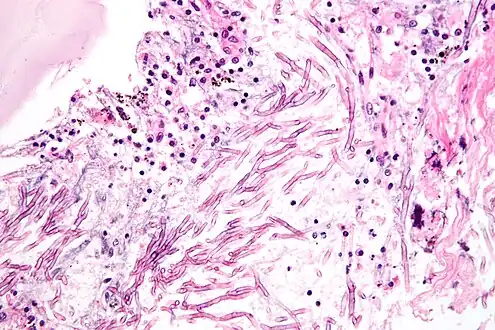

Cryptococcus

Cryptococcus neoformans can cause a severe form of meningitis and meningo-encephalitis in patients with HIV infection and AIDS. The majority of Cryptococcus species live in the soil and do not cause disease in humans. Cryptococcus neoformans is the major human and animal pathogen. Papiliotrema laurentii and Naganishia albida, both formerly referred to Cryptococcus, have been known to occasionally cause moderate-to-severe disease in human patients with compromised immunity. Cryptococcus gattii is endemic to tropical parts of the continent of Africa and Australia and can cause disease in non-immunocompromised people.[1]

Infecting C. neoformans cells are usually phagocytosed by alveolar macrophages in the lung.[11] The invading C. neoformans cells may be killed by the release of oxidative and nitrosative molecules by these macrophages.[12] However some C. neoformans cells may survive within the macrophages.[11] The ability of the pathogen to survive within the macrophages probably determines latency of the disease, dissemination and resistance to antifungal agents. In order to survive in the hostile intracellular environment of the macrophage, one of the responses of C. neoformans is to upregulate genes employed in responses to oxidative stress.[11]